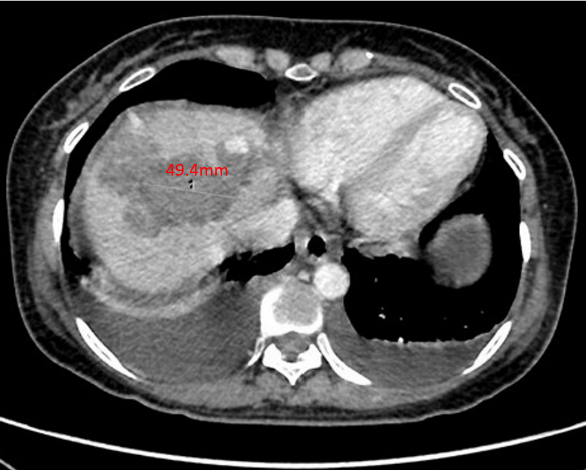

绒患者,张某,女,51岁。主诉:停经伴左中下腹痛4+月 现病史:患者既往月经规律,周期30天,LMP 2021年7月14日。停经后无恶心、呕吐等不适。G3P2A1,足月顺产两次,末次妊娠为7年前,行人工流产终止妊娠,此后以避孕套避孕。4月余前无明显诱因出现左中下腹隐痛,休息后可缓解,无进行性加重,无排便习惯改变等。2021年10月30日就诊于当地医院,彩超示:肝内多发高回声结节,血管瘤?其他不排。左侧腹腔内低回声包块,性质待定,腹腔少量积液。CT提示:左侧腹部占位性病变,考虑来源于腹腔,性质待查,纤维瘤?间质瘤?其他?转诊至当地上级医院,行电子直-结肠镜示:乙状结肠病变性质待查。CT示:1.左侧腹腔内肿块灶:间质瘤?炎性肌纤维母细胞瘤?2.肝内多发结节灶:转移瘤;3.子宫肌层内结节灶:子宫肌瘤?4.右侧附件区不规则肿块:粘液囊腺瘤可能性大;5.宫颈左后上方结节灶:转移瘤?6.盆腔少量积液;7.腹腔内多发小淋巴结。在超声引导下行左上腹腹腔肿块穿刺活检,穿刺组织3条,全部为凝固性坏死组织,倾向恶性肿瘤。2021年11月1日血清hCG 830 mIU/ml。2021年11月8日再次转诊至广州某医院,行肝部肿物穿刺,病理示:(肝肿物)结合免疫组化[β-HCG(+),GATA-3(+),p63(部分+)]考虑为绒毛膜上皮癌可能性大。2021年11月17日血清hCG >100万 mIU/ml。为进一步诊治,请我院进行院际会诊后,予以EP方案化疗1程后转入我科。 月经婚育史:12岁初潮,周期30天,经期5天,LMP 2021年7月14日,量中,无痛经。生育史同前。 个人史和家族史:无特殊。 体格检查:T 36.3℃,P 102次/分,R 20次/分,BP 120/80mmHg,身高156cm,体重50kg。左侧中下腹部触诊可及一约15cm×10cm边界不规则的质硬肿物,活动度差,轻压痛。 妇科检查:外阴未见异常;阴道通畅,各壁未见紫蓝色结节;宫颈正常大小,光滑,无接触性出血;宫体前位,大小基本正常,活动度差;双侧附件区未及异常肿物;三合诊:道格拉斯窝处可及一边界欠清肿物,触痛不明显,双侧宫旁无增厚,指套退出直肠无血染。 辅助检查: 全腹部CT平扫+增强+三维重建:腹腔大量积液,脂肪间隙模糊并多发渗出;肝内多发转移瘤并部分瘤内出血;左中腹肝胃间隙、脾胃间隙及子宫直肠间隙肿块,考虑转移瘤。 胸部CT:双肺散在实性结节,考虑转移瘤。 头颅MR平扫+增强:未见异常。